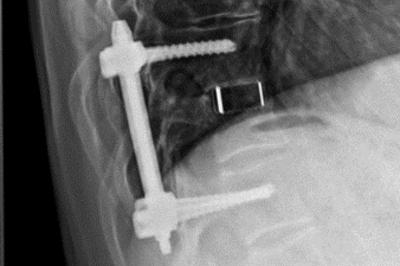

• Wirbelkörperersatz

Seitliches Röntgenbild Wirbelkörperersatz

Versorgung mit Schrauben-Stab-System, Spinalkanaldekompression und Wirbelkörperersatz